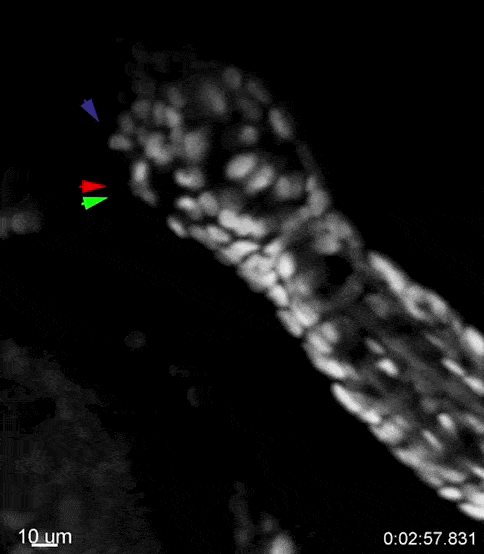

Le encontraron la vuelta a la calvicie (NYTimes $): Observando folículos en pelos de ratones modificados genéticamente para “envejecer” rápido, observaron un evento poco usual que da luz a un nuevo entendimiento de la caída del pelo y, por ende, del envejecimiento en sí. ¿Qué se vió? Resulta que gracias a reducción determinados genes (Foxc1 y Nfatc1), los folículos de pelo se achican. Pudieron observar que en este estado las células madre se desprenden (si, cosa que no esperaba que pasara) del folículo generando así la desintegración del folículo. Este estudio arroja luz sobre una actividad hasta ahora desconocida de las células epiteliales que escapan de su nicho como mecanismo subyacente a la reducción de células madre y la degeneración tisular. La identificación de células epiteliales sin hogar en tejidos envejecidos proporciona una nueva perspectiva para comprender las enfermedades asociadas al envejecimiento. (Link al documento publicado en Nature.com)